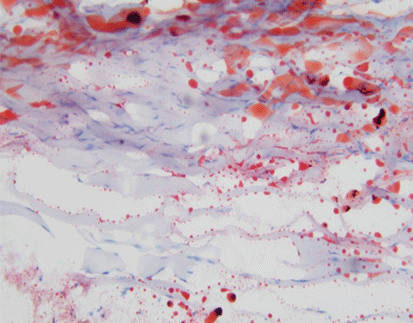

SPECIAL STAINS